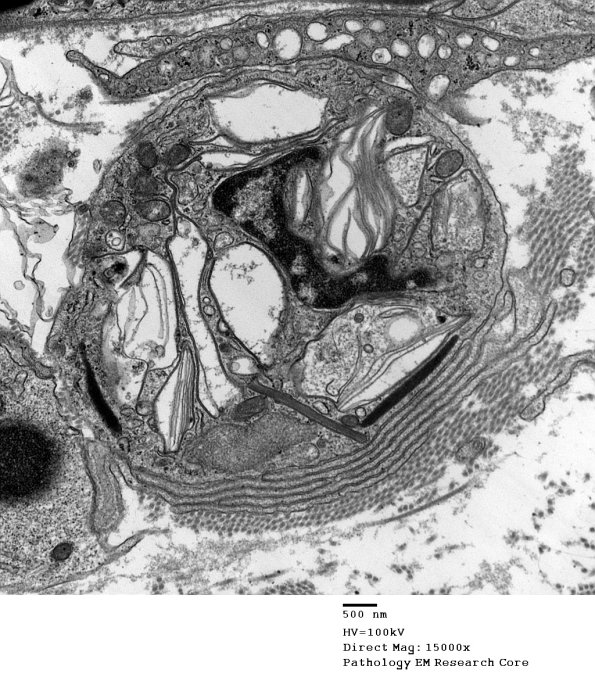

Higher magnification of image #3D1. (electron micrograph)

3D2 Axonal Degeneration (Case 4) EM 113 - Copy